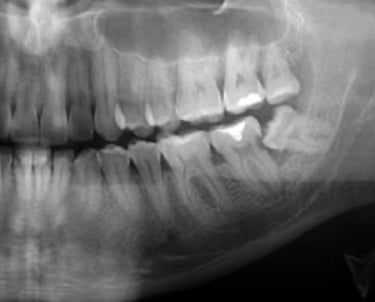

Pacientes Sistêmicos (com doenças crônicas, com diabetes, hipertensão, cardiopatias) e acamados muitas vezes apresentam mais risco de complicações orais. A falta de tratamento adequado pode transformar um problema dental em porta de entrada para infecções graves.

A cirurgia odontológica em pacientes sistêmicos e acamados e essencial para prevenir infecções , controlar dor e proteger a saude geral. Quando bem indicada e planejada, torna-se um procedimento de segurança, cuidado integral e qualidade de vida.